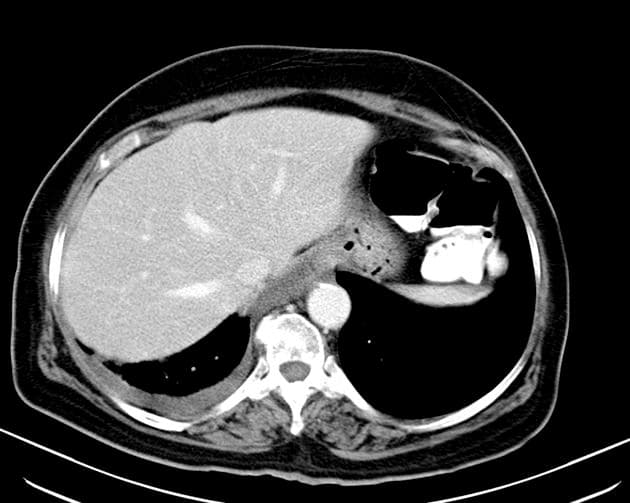

Chẩn đoán & Phát hiện

Thành dạ dày dày không đối xứng và tăng quang mạnh do thâm nhiễm u tại tâm vị và phần gần bờ cong nhỏ, kèm theo nhiều hạch bạch huyết lớn quanh dạ dày. Các hạch bạch huyết lớn này tiếp xúc sát với thùy gan trái và tuyến thượng thận trái, cùng với tình trạng tuyến thượng thận trái lớn nhẹ, gợi ý có sự xâm lấn tại chỗ. Có một hạch bạch huyết lớn nằm ở chuỗi hạch dưới hoành phải. Ngoài ra, có một khối lớn, không đồng nhất với bờ không đều ở gan, biểu hiện tăng quang ngoại vi sớm kèm washout muộn và hoại tử trung tâm rộng. Có tình trạng giãn nhẹ ống mật trong gan ở vùng ngoại vi của khối u. Phần còn lại của gan bình thường và không có dấu hiệu của xơ gan nền. Có một nang kích thước 8 mm ở lách. Một vài nang nhỏ cạnh bể thận được ghi nhận ở cả hai thận, quan sát rõ hơn trên các hình ảnh thì bài tiết. Bệnh nhân đã được thực hiện sinh thiết khối u dạ dày qua nội soi và sinh thiết kim lõi khối u gan dưới hướng dẫn siêu âm. Kết quả giải phẫu bệnh và hóa mô miễn dịch xác nhận ung thư biểu mô tuyến dạng tế bào gan nguyên phát của dạ dày kèm di căn gan. THẢO LUẬN: Trường hợp này minh họa một ca ung thư biểu mô tuyến dạng tế bào gan tiến triển ác tính của dạ dày, xuất phát từ tâm vị và phần gần bờ cong nhỏ ở một bệnh nhân lớn tuổi, biểu hiện với di căn hạch vùng tiến triển và di căn gan lớn, nồng độ AFP huyết thanh cao, cùng các đặc điểm hình ảnh có thể rất giống với ung thư biểu mô tế bào gan nguyên phát. Ung thư biểu mô tuyến dạng tế bào gan của dạ dày là một loại ung thư dạ dày hiếm gặp, có độ ác tính cao, về mặt mô học giống với ung thư biểu mô tế bào gan và thường sản sinh alpha-fetoprotein (AFP). Nó chiếm khoảng 1% các trường hợp ung thư dạ dày và thường được phát hiện ở giai đoạn muộn với di căn gan và di căn hạch. Ung thư biểu mô tế bào gan nguyên phát và ung thư biểu mô tuyến dạng tế bào gan của dạ dày di căn gan có thể có hình thái rất giống nhau; tuy nhiên, chúng khác nhau về bối cảnh lâm sàng, đặc điểm hình thái và hóa mô miễn dịch.